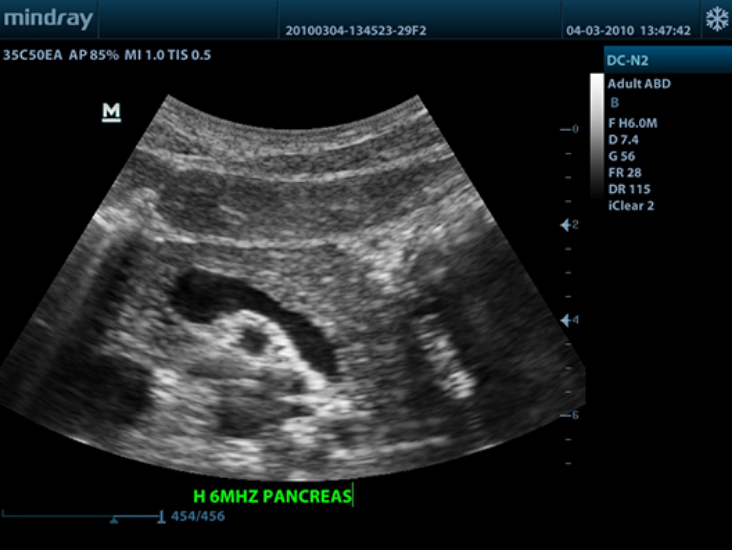

DC-N2

Color Doppler within Reach

DC-N2 offers a unique combination of relevant technology, quality and affordability. Be it an experienced ultrasound professional or a beginner, the DC-N2, with its unique self-learning software and advanced imaging technologies can be used across multiple clinical settings. With a user-friendly control panel and a user-centric workflow system, the DC-N2 can be well trusted for its performance and ease of use.

PSH? (Phase Shift Harmonic Imaging)

Purified Harmonic Imaging for better contrast resolution providing clearer images with excellent resolution and less noise.

iClear?

Gain improved image quality based on auto structure detection.

- Sharper & Continuous Edges

- Smooth Uniform Tissues

- Cleaner ŌĆśno echo areasŌĆÖ